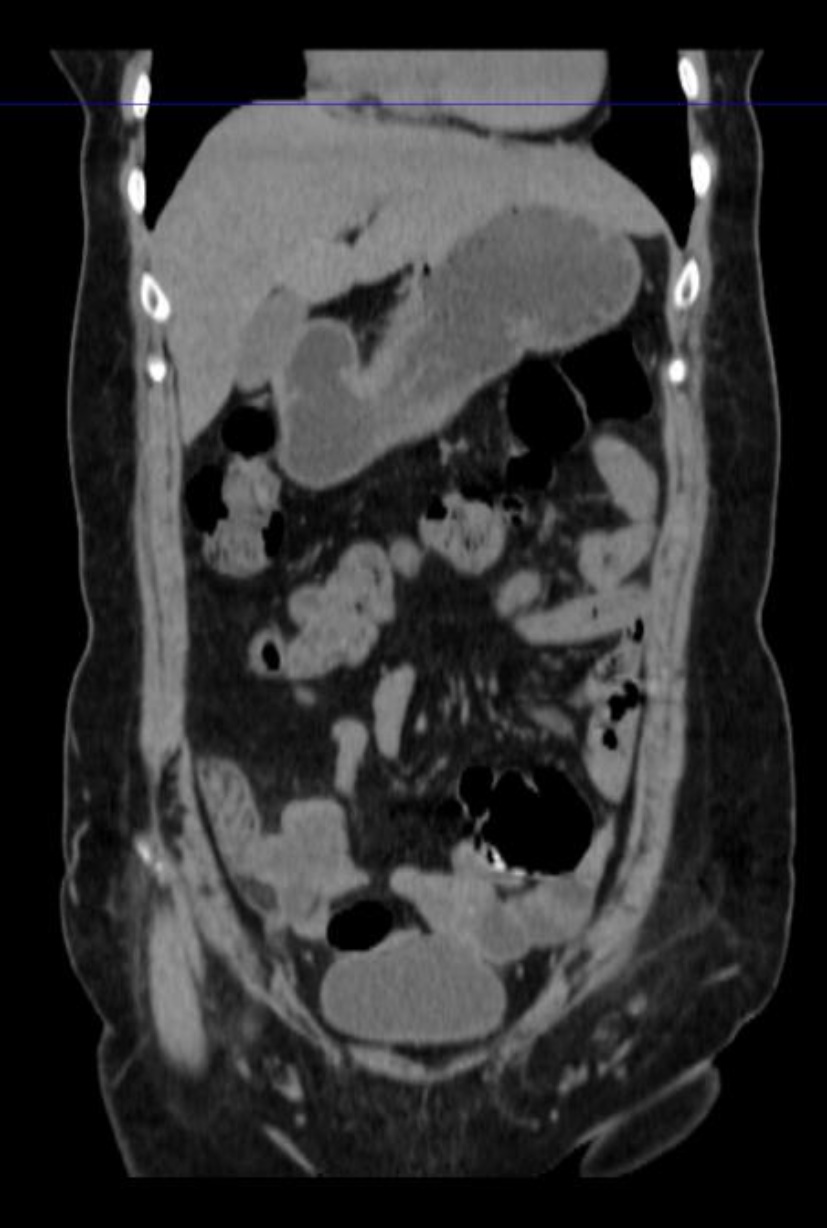

出院后患者为行扩大根治手术,来我院就诊。给进一步完善相关检查,腹部增强CT示:

患者阑尾未见明确显示,相应区短条状高密度影,周围条片及淋巴结影,边欠清,部分轻度强化征象,局部肠壁模糊,右下腹肠系膜及大网膜条片影,边欠清。区段小肠肠壁明显增厚,考虑肿瘤可能性大(见图4(a)图4(b))。经多学科讨论后,考虑患者阑尾肿瘤合并小肠肿瘤可能性大,各项术前检查未见明显转移征象,建议再次行手术探查。术中见:肝周及盆底血性积液,量约100 ml,部分小肠黏连与腹壁原切口下方,顿性分离黏连肠管,部分小肠、大网膜黏连固定于右下腹回盲部,松解黏连后,见回盲部、临近小肠系膜、大网膜及右侧腹壁触及质硬结节,距回盲部2 m处小肠肠管明显增粗、质硬,肝脏表面光滑,无明显占位。给予切除距回盲部远端10 cm升结肠及近端10 cm回肠,行回肠及升结肠吻合。切除距回盲部2 m处病变小肠,行小肠吻合。术后病理示:(距回盲部2 m处小肠):黏液癌(隆起型,3 × 2 cm),肿瘤侵透浆膜,脉管癌栓(−),神经侵犯(+),两侧手术切缘未见癌累及,肠周淋巴结内未见癌转移(0/2) (见图5图6)。(回盲部小肠):送检小肠组织,黏膜慢性炎,浆膜面及肠系膜内出血、纤维组织及间皮增生并见少许无上皮黏液,两侧切缘未见癌累及,肠周淋巴结内未见癌转移(0/10)。病理分期:pT4bN0Mx。(右半结肠)送检肠管组织,浆膜面见少量异型腺体浸润,意见为癌。周围组织呈异物肉芽肿性炎,两侧手术切缘未见癌累及,肠周淋巴结内未见癌转移(0/21)。(腹膜结节)送检组织内纤维组织结节状增生。(大网膜)网膜组织内见多处纤维组织增生伴异物巨细胞反应。经多学科会诊讨论后,考虑患者诊断原发肿瘤来自小肠,阑尾肿瘤为小肠侵犯所致。术后患者于肿瘤科行3周期Xelox方案化疗:奥沙利铂130 mg/m2,静脉输注2 h,第1天。卡培他滨每次1000 mg/m2,每日2次,第1~14天。患者术后随访至今未见异常。

(a) (b)

Figure 4. Abdominal CT (Before the second surgery)

4. 腹部CT(第二次手术前)